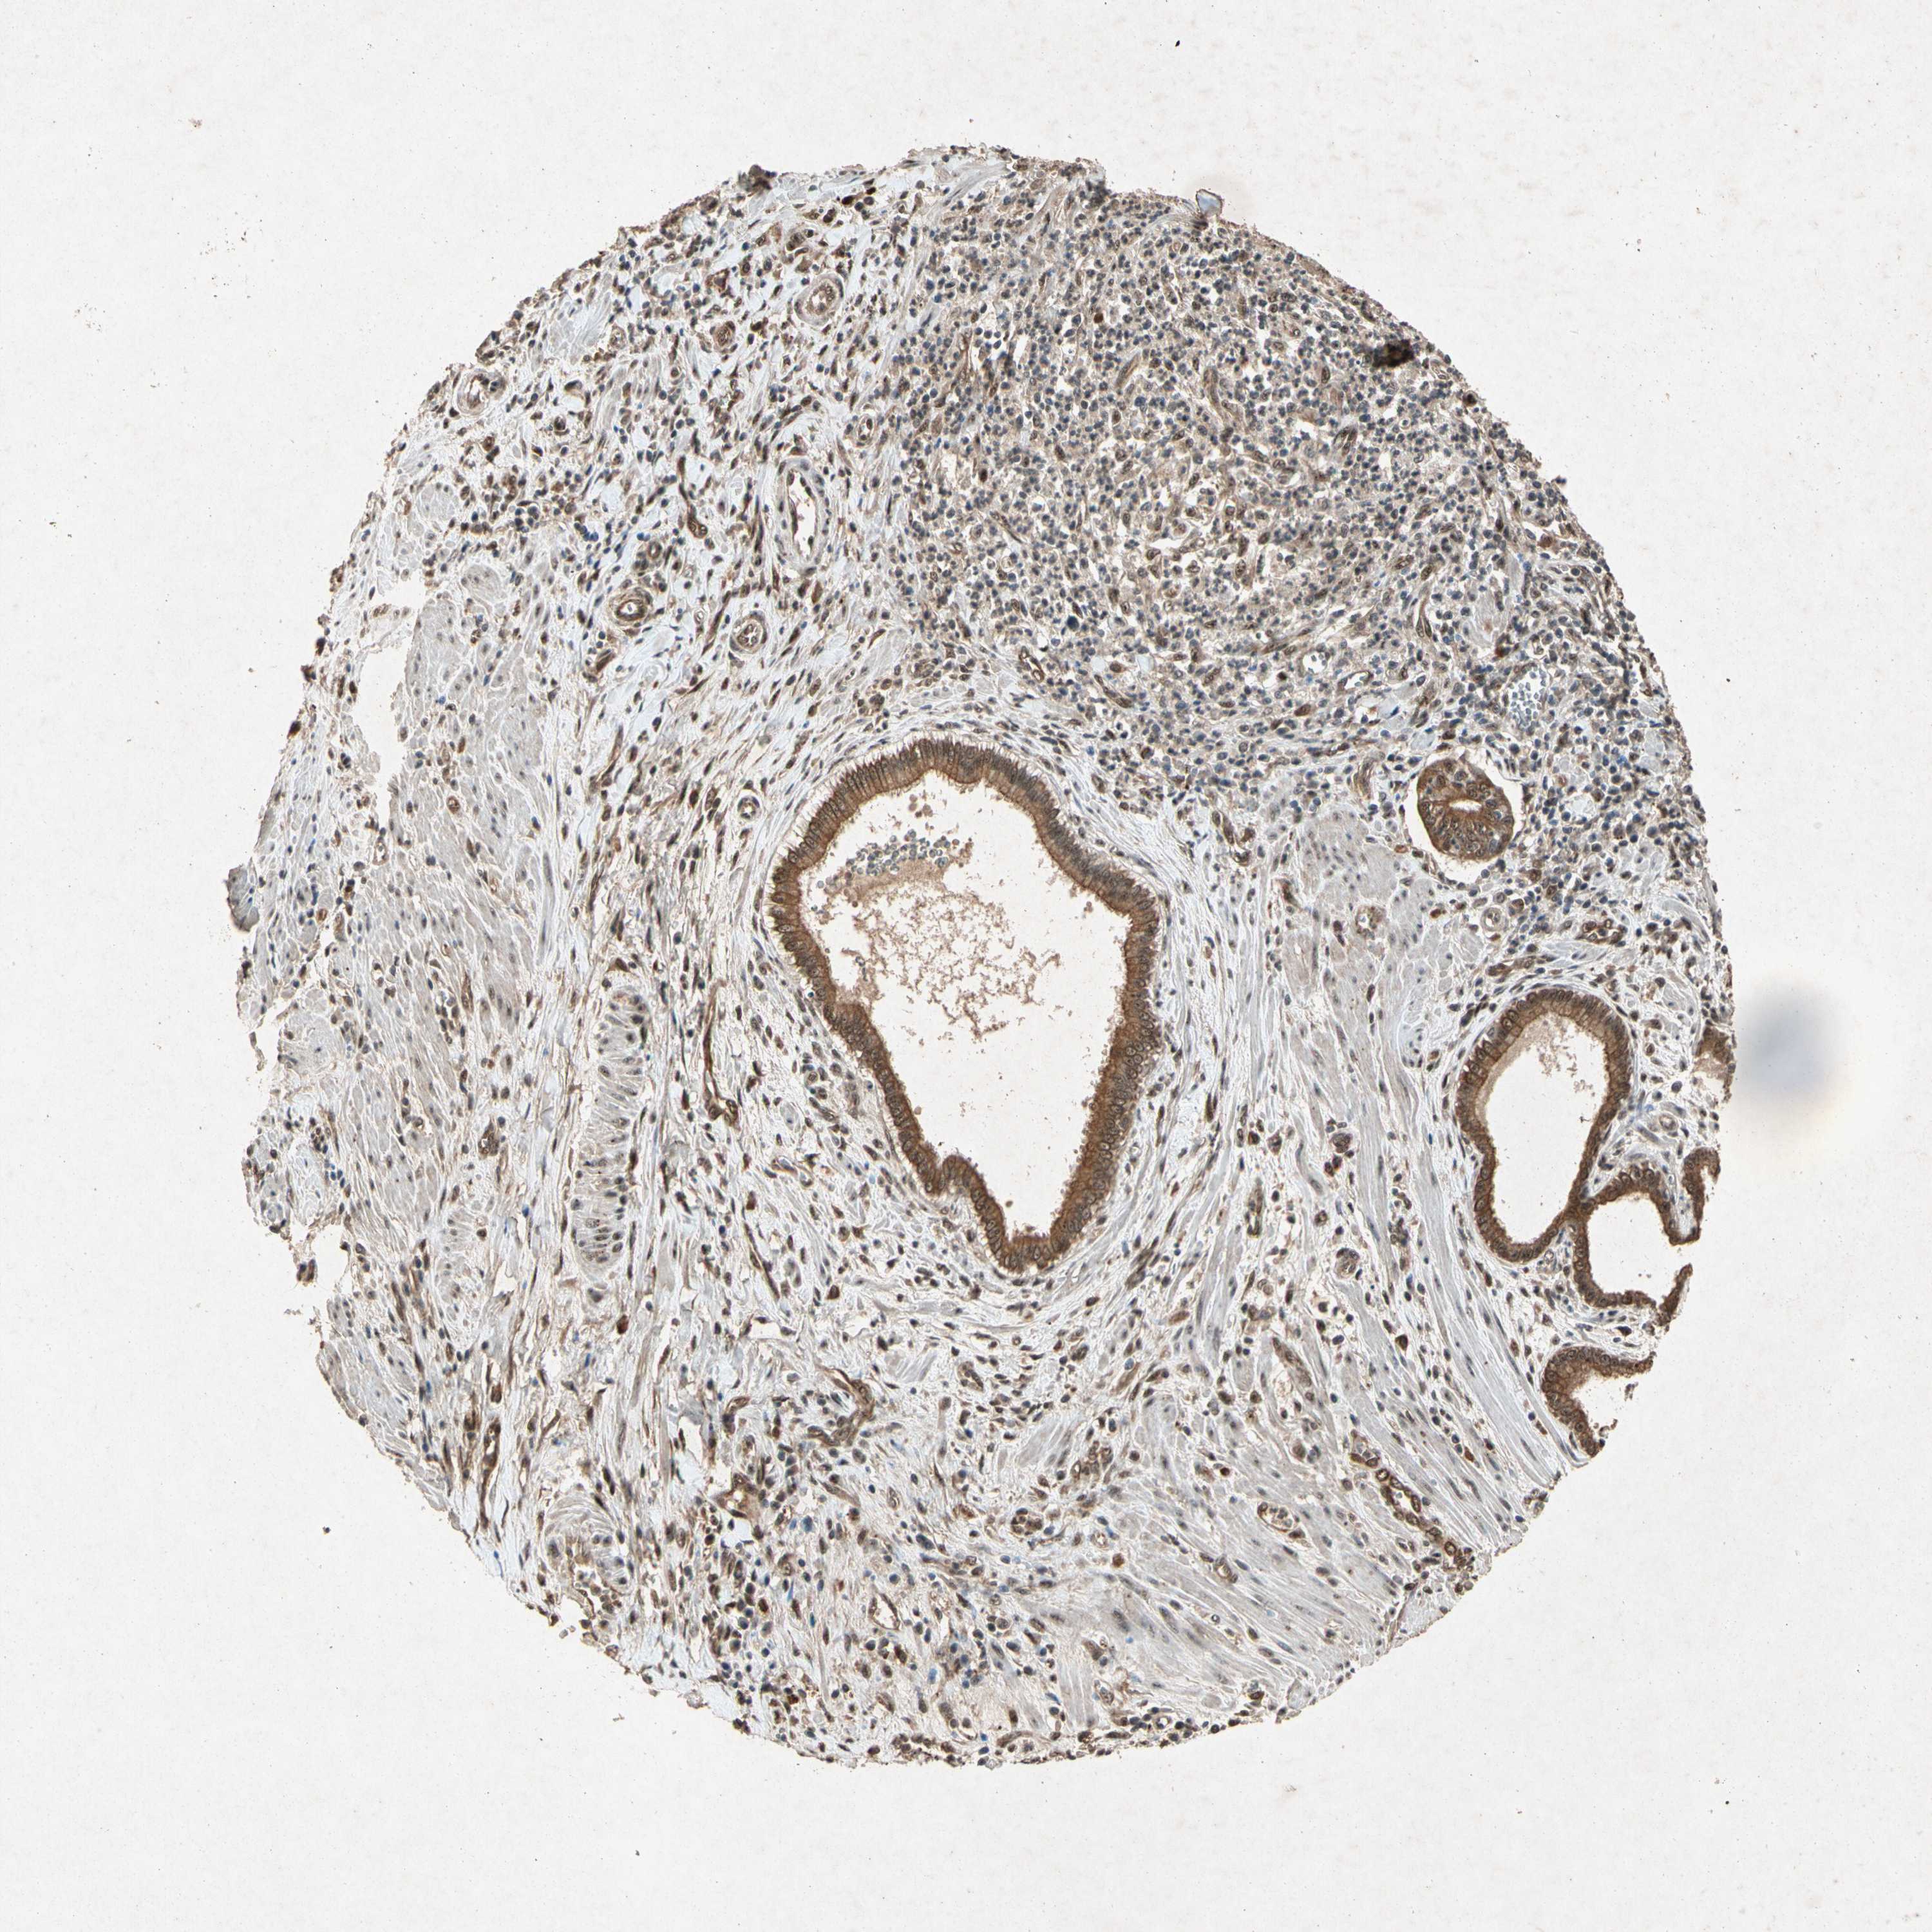

PANCREATIC CANCER - Protein expressioni

A mouse-over function shows sample information and annotation data. Click on an image to view it in a full screen mode. Samples can be filtered based on level of antibody staining by selecting one or several of the following categories: high, medium, low and not detected. The assay and annotation is described here.

Note that samples used for immunohistochemistry by the Human Protein Atlas do not correspond to samples in the TCGA dataset.

Antibody stainingi

Antibody staining in the annotated cell types in the current human tissue is reported as not detected, low, medium, or high, based on conventional immunohistochemistry profiling in selected tissues. This score is based on the combination of the staining intensity and fraction of stained cells.

Each image is clickable and will lead to virtual microscopy that enables deeper exploration of all samples and also displays staining intensity scores, fraction scores and subcellular localization as well as patient and tissue information for each sample.

Antibody HPA008312

Antibody CAB010194

Antibody CAB016304

Staining

High

Medium

Low

Not detected

Intensity

Strong

Moderate

Weak

Negative

Quantity

>75%

75%-25%

<25%

None

Location

Nuclear

Cytoplasmic/membranous

Cytoplasmic/membranous,nuclear

Adenocarcinoma, NOS

Adenocarcinoma, metastatic, NOS